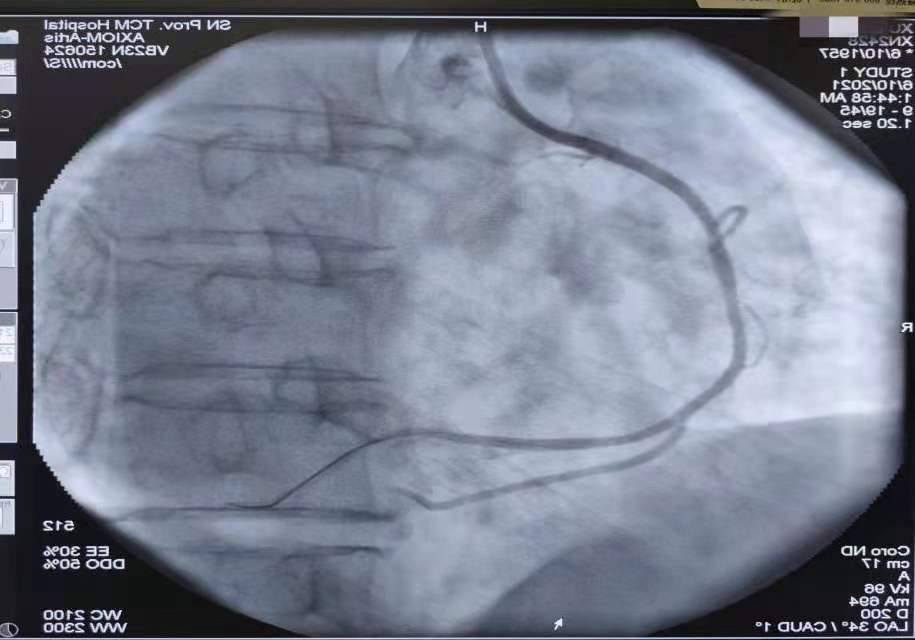

PCI术后